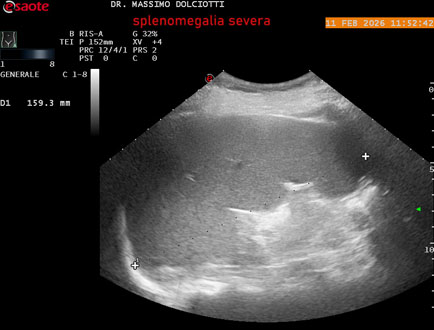

Data inserimento: 18/02/2026

Ecografia del: 11/02/2026

Strumento: Esaote MyLab Eight

Sonda: Conevx Multifrequenza 1-8 MHz

Età Paziente: F 68 anni

Motivazione dell'esame: follow up di splenomegalia.

Commento all'esame: le immagini ed il video documentano la milza con ecostruttura normale e morfovolumetria superiore alla norma, con diametro bipolare di 159 mm (v.n. 70-120 mm) ed area di sezione di 101 centimetri quadri (v.n. < 47 centimetri quadri).

Conclusioni: splenomegalia di severa entità (severe splenomegaly).